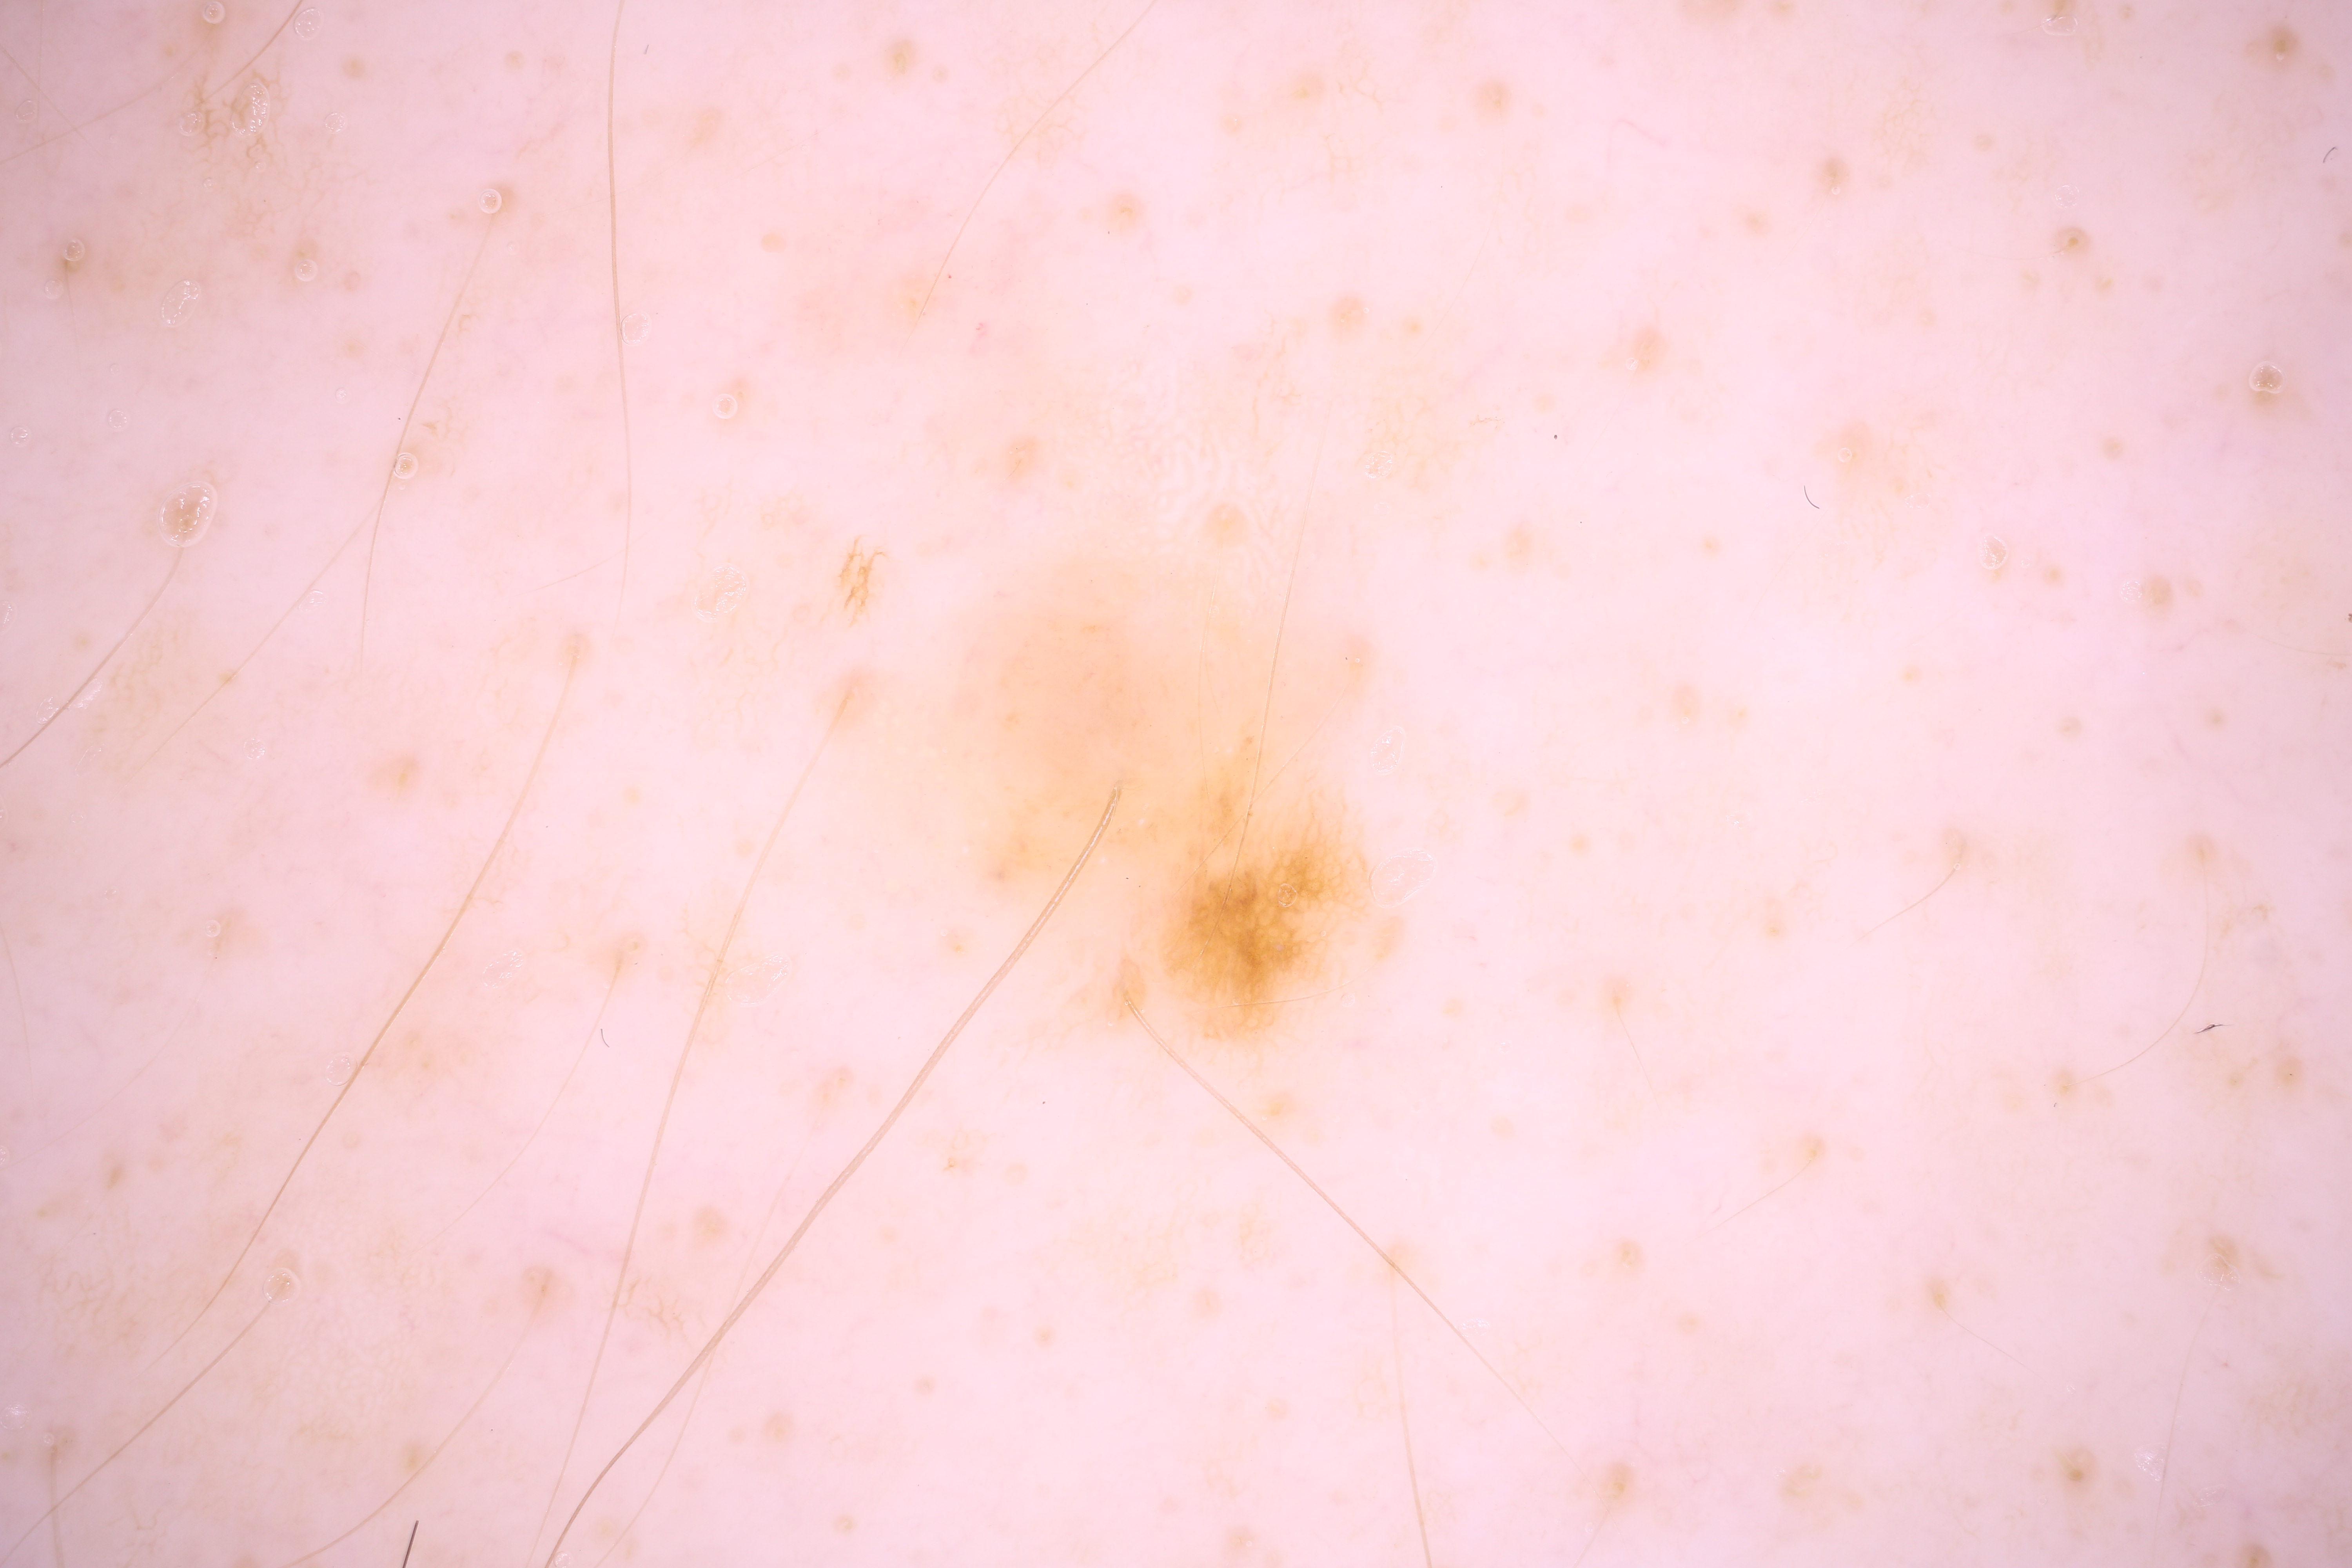

{

"acquisition_day": 9,

"age_approx": 55,

"anatom_site_general": "upper extremity",

"concomitant_biopsy": false,

"diagnosis_1": "Benign",

"diagnosis_confirm_type": "single image expert consensus",

"image_manipulation": "instrument only",

"image_type": "dermoscopic",

"lesion_id": "IL_2911313",

"patient_id": "IP_7770500",

"sex": "male"

}